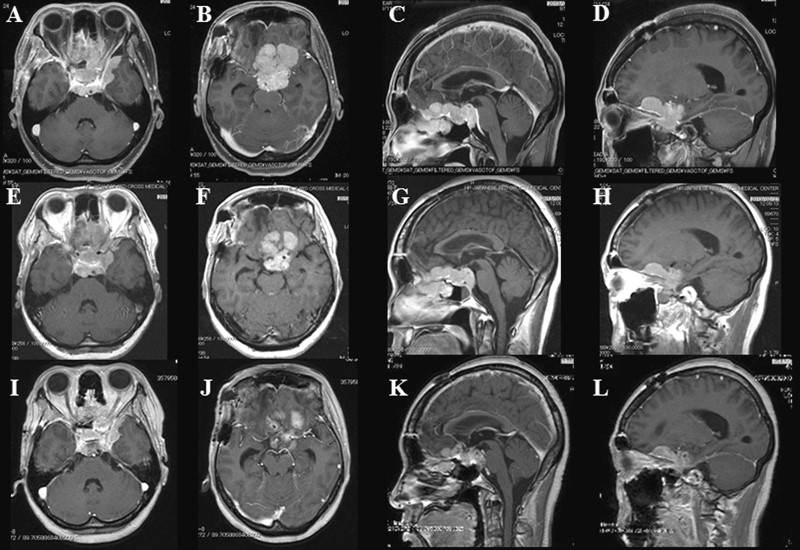

BNCT硼中子俘获如何一步步治疗脑瘤?附临床疗效汇总

BNCT治疗脑瘤。关于癌症放疗,质子治疗的前沿和先进性渐渐广为熟知。实际上,还有一种比质子更为精准、副作用更低的放疗黑科技可惠及更多癌症患者,也就是大家可能已有耳闻的硼中子俘获(BNCT)。尽管该技术早几年都处在临床试验阶段,但已有越来越多的研究证实,BNCT之于脑肿瘤及其他一些癌症的有效性。

传统放疗“杀敌一千,自损八百”,质子治疗极大提高了放疗的精准性,而BNCT的安全性则更高。BNCT所产生的α粒子和锂离子射程很短,只有一个细胞的长度,所以只“杀死”癌细胞而不损伤周围细胞组织。对于脑胶质瘤、黑色素瘤和头颈部复发肿瘤,BNCT是非常有效的放疗手段,并试治肝癌、肺癌、胰腺癌等脏器肿瘤。

BNCT治疗脑肿瘤的临床研究数据